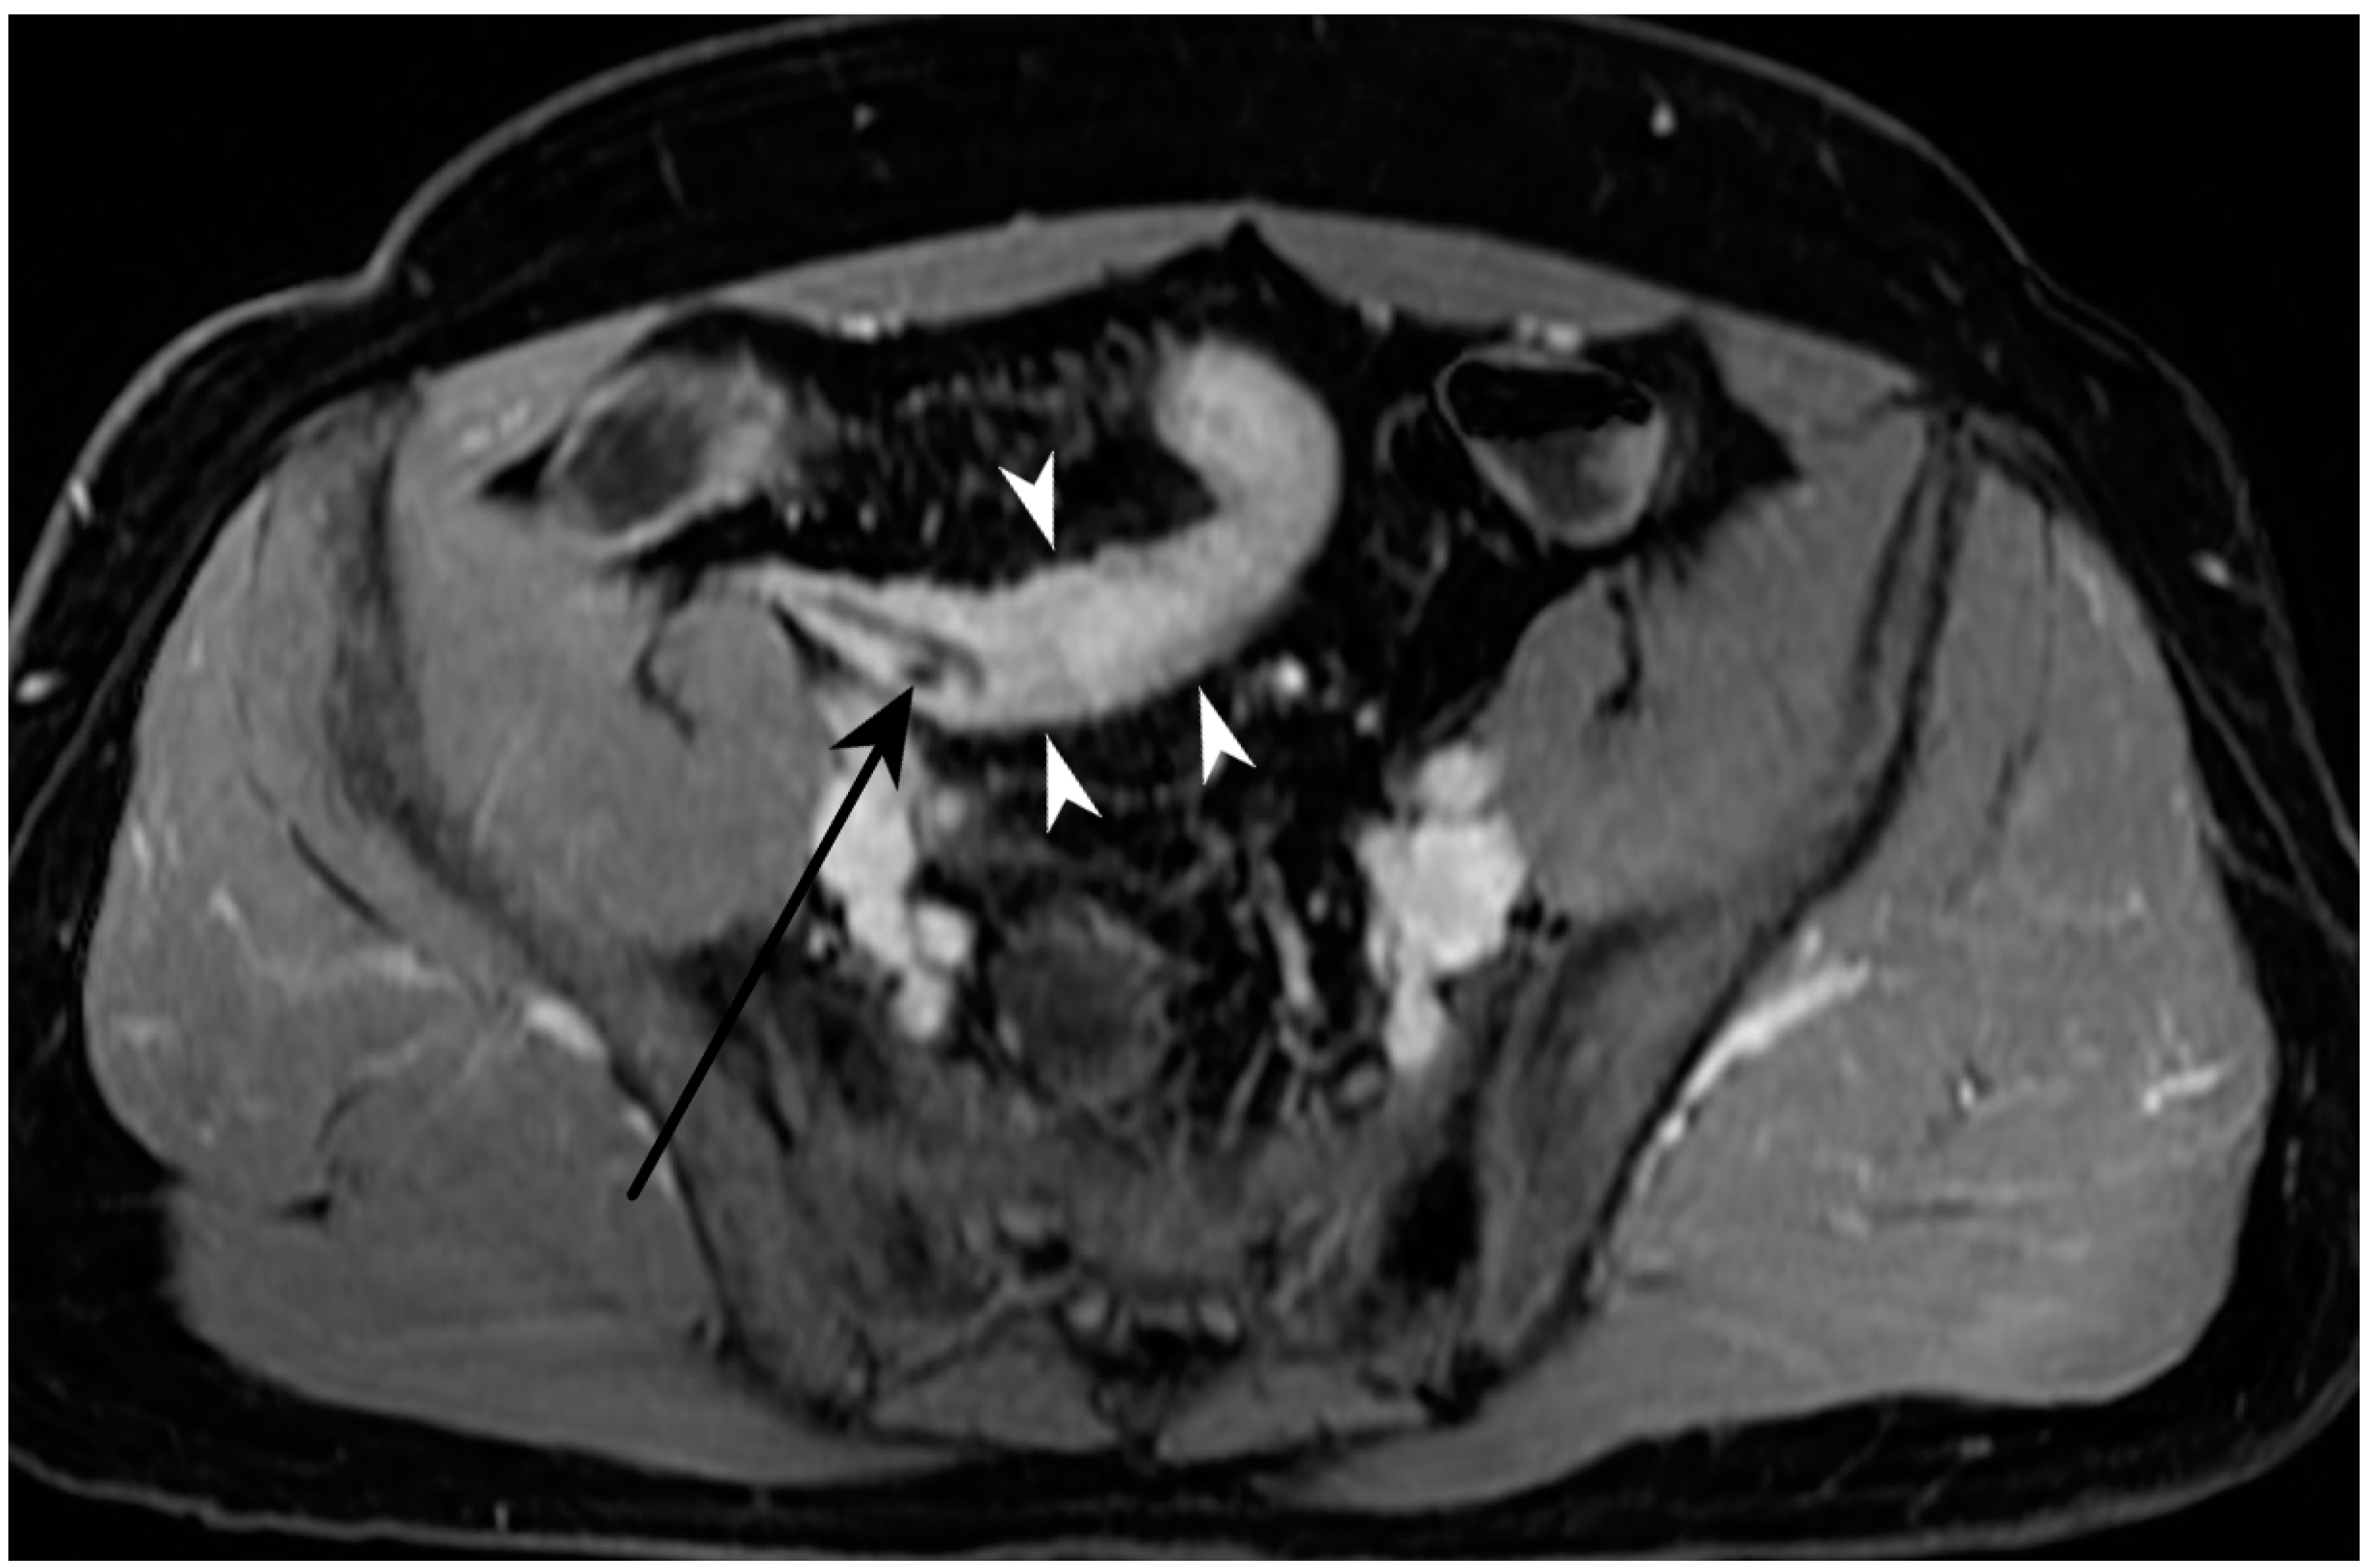

5.3. Fistulising/Perforating Subtype